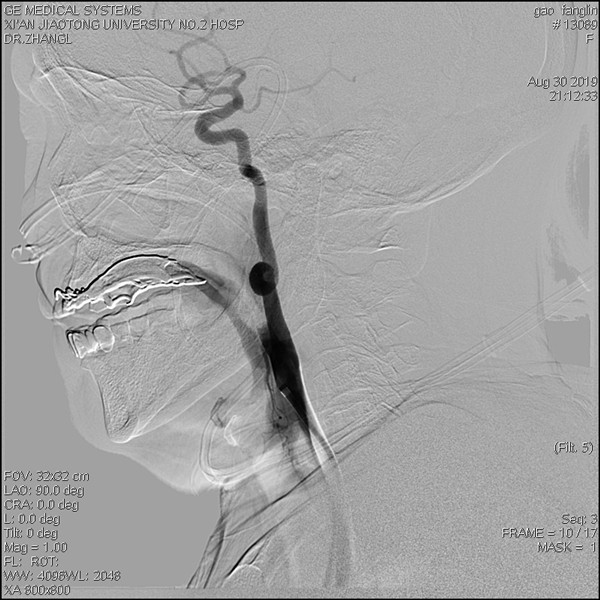

取栓术后颈内动脉内血栓消失

造影见右侧颈内动脉起始段内大量血栓